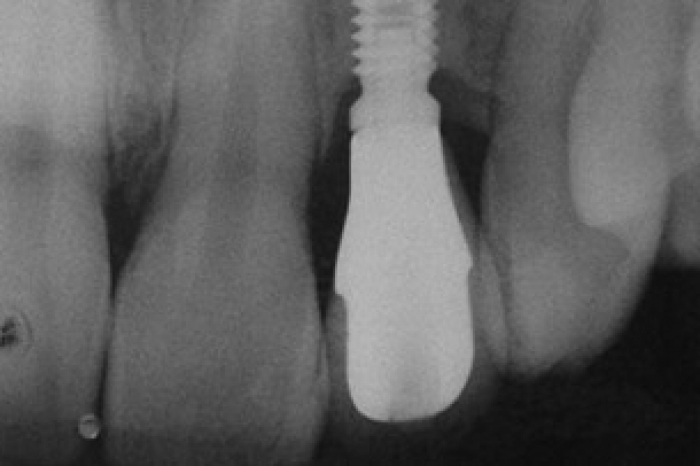

Imagens de implantes em incisivo lateral direito e esquerdo instalados